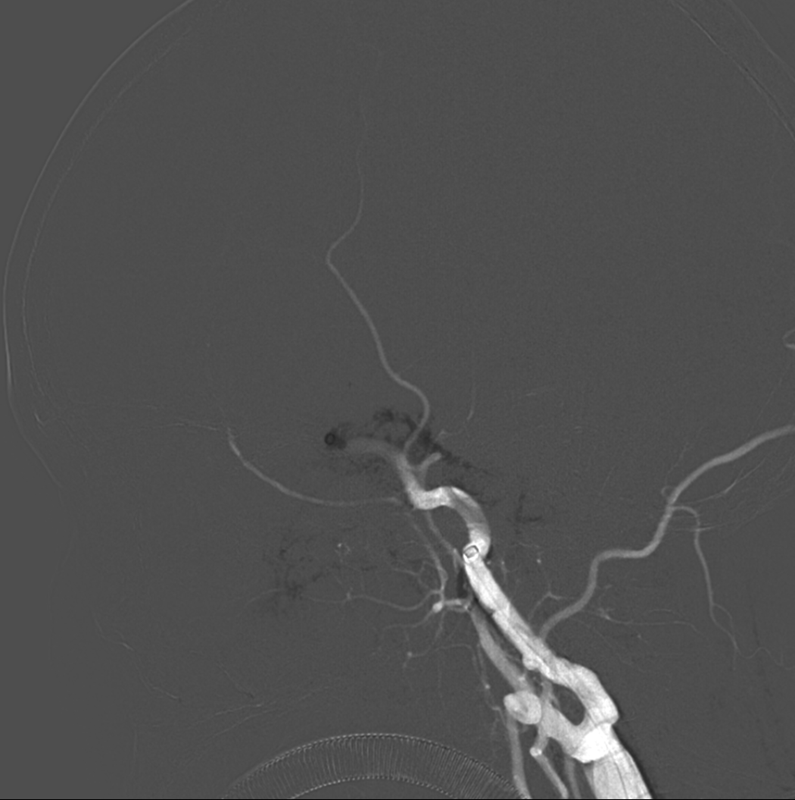

DSA

8月25日.gif

Skathi PRO颅内血栓抽吸导管裸奔上到颈内动脉交通段。image.pngTarvos微导丝成袢到位后带Velleda微导管到位

释放ET取栓支架后,在支架锚定下,Skathi PRO颅内血栓抽吸导管到位

SWIM技术抽拉结合取栓